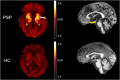

Progressive supranuclear palsy (PSP) is a 4-repeat tauopathy movement disorder that can be imaged by the 18F-labeled tau PET tracer 2-(2-([18F]fluoro)pyridin-4-yl)-9H-pyrrolo[2,3-b:4,5-c']dipyridine (18F-PI-2620). The in vivo diagnosis is currently established on clinical grounds and supported by midbrain atrophy estimation in structural MRI. Here, we investigate whether 18F-PI-2620 tau PET has the potential to improve the imaging diagnosis of PSP. Methods: In this multicenter observational study, dynamic (0-60 min after injection) 18F-PI-2620 PET and structural MRI data for 36 patients with PSP, 22 with PSP-Richardson syndrome, and 14 with a clinical phenotype other than Richardson syndrome (i.e., variant PSP) were analyzed along with data for 10 age-matched healthy controls (HCs). The PET data underwent kinetic modeling, which resulted in distribution volume ratio (DVR) images. These and the MR images were visually assessed by 3 masked experts for typical PSP signs. Furthermore, established midbrain atrophy parameters were measured in structural MR images, and regional DVRs were measured in typical tau-in-PSP target regions in the PET data. Results: Visual assessments discriminated PSP patients and HCs with an accuracy of 63% for MRI and 80% for the combination of MRI and 18F-PI-2620 PET. As compared with patients of the PSP-Richardson syndrome subgroup, those of the variant PSP subgroup profited more in terms of sensitivity from the addition of the visual 18F-PI-2620 PET to the visual MRI information (35% vs. 22%). In quantitative image evaluation, midbrain-to-pons area ratio and globus pallidus DVRs discriminated best between the PSP patients and HCs, with sensitivities and specificities of 83% and 90%, respectively, for MRI and 94% and 100%, respectively, for the combination of MRI and 18F-PI-2620 PET. The gain of sensitivity by adding 18F-PI-2620 PET to MRI data was more marked in clinically less affected patients than in more affected patients (37% vs. 19% for visual, and 16% vs. 12% for quantitative image evaluation). Conclusion: These results provide evidence for an improved imaging-based PSP diagnosis by adding 18F-PI-2620 tau PET to structural MRI. This approach seems to be particularly promising at earlier disease stages and could be of value both for improving early clinical PSP diagnosis and for enriching PSP cohorts for trials of disease-modifying drugs.